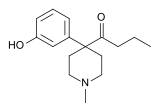

4-Phenylpiperidines

Ketobemidones

Structures

Others

Structures

| Other phenylpiperidines | |||

|---|---|---|---|

Alvimopan Alvimopan |

Loperamide Loperamide |

LS-115509 LS-115509 |

Picenadol Picenadol |